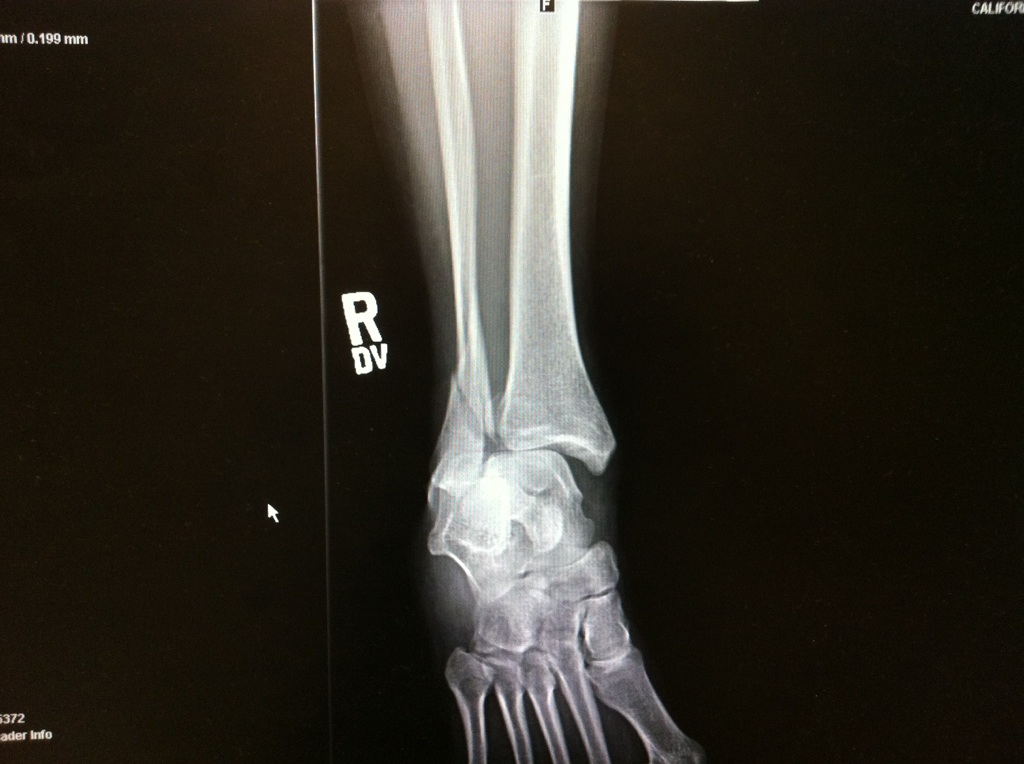

From brokenrightankle.blogspot.com

My Broken Ankle =( ER Broken ankle, fractured heel, dislocated, and Fractured Heel No Surgery Surgery to repair a calcaneus fracture can restore the normal shape of the bone but is sometimes associated with complications, such as wound healing problems, infection, and nerve damage. if your heel bone (calcaneus) gets fractured, either due to a traumatic injury or as a result of chronic overuse or repetitive stress, recovery can be a long and difficult. Fractured Heel No Surgery.